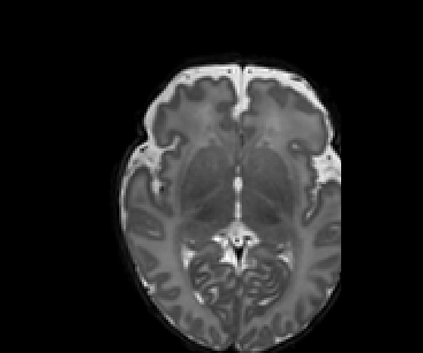

Real-world settings often do not allow acquisition of high-resolution volumetric images for accurate morphological assessment and diagnostic. In clinical practice it is frequently common to acquire only sparse data (e.g. individual slices) for initial diagnostic decision making. Thereby, physicians rely on their prior knowledge (or mental maps) of the human anatomy to extrapolate the underlying 3D information. Accurate mental maps require years of anatomy training, which in the first instance relies on normative learning, i.e. excluding pathology. In this paper, we leverage Bayesian Deep Learning and environment mapping to generate full volumetric anatomy representations from none to a small, sparse set of slices. We evaluate proof of concept implementations based on Generative Query Networks (GQN) and Conditional BRUNO using abdominal CT and brain MRI as well as in a clinical application involving sparse, motion-corrupted MR acquisition for fetal imaging. Our approach allows to reconstruct 3D volumes from 1 to 4 tomographic slices, with a SSIM of 0.7+ and cross-correlation of 0.8+ compared to the 3D ground truth.